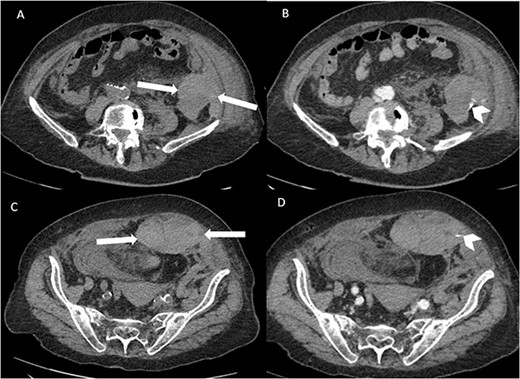

Suspecting internal haemorrhage, contrast-enhanced computed tomography (CECT) of the abdomen and pelvis was arranged. The CT images showed the presence of multiple haematomas with evidence of active bleeding (Figs 1 and 2).

Axial non-contrast CT abdomen and pelvis at the level of acetabulum. Rectus sheath haematoma (chevron) that appears to have dissected through the rectus sheath into the extraperitoneal pelvic space (arrows).